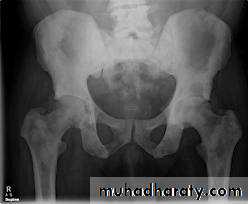

Radiology of urinary system

Dr. Sameer Abdul Lateef* Infestation by Schist. Haematobium.

*The ova deposited into sub-mucosa of urinary bladder and to less extent at the wall of ureters .*The ova calcify and excrete toxin producing necrosis of tissue lead to granulomatous tubercles and extensive fibrosis .

*Calcification is very common and important diagnostic findings. Very common in bladder ,less frequent in lower ureters ,but in advanced case involve the whole length of ureter .

*The appearance depends on degree of fullness of bladder ; thin linear opacity outlining bladder wall.

Empty bladder shows crowded linear opacities with calcified plaques.

Urinary Schistomiasis

• IVU: Early stage –cobble stone Later filling defects due to graneulomatos papilloma Carcinoma is important complication Ureters : dilated and tortuousIn early stage hydroureter and hydronephrosis + refluxSPACE OCCUPING LESION